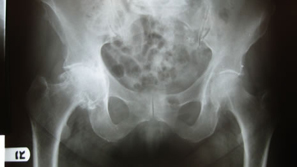

Our last ENEWS-Update January 6, 2010 highlighted Dr. Ed McPherson in evaluating Tissue Sparing Hip Techniques using a small posterior approach. This edition will highlight a single incision anterior approach performed by Dr. Bradley Walter.

Dr. Walter has been interested in tissue sparing approaches for THA and has been using the single anterior approach and short cementless stems for the past few years.

| No special table or instruments are required if a short stem is used. |

Excellent exposure of the acetabulum even with a high neck osteotomy. |

| High neck cut |

| Supine position provides good orientation for the socket preparation and insertion. |

Good exposure of the proximal femur. |